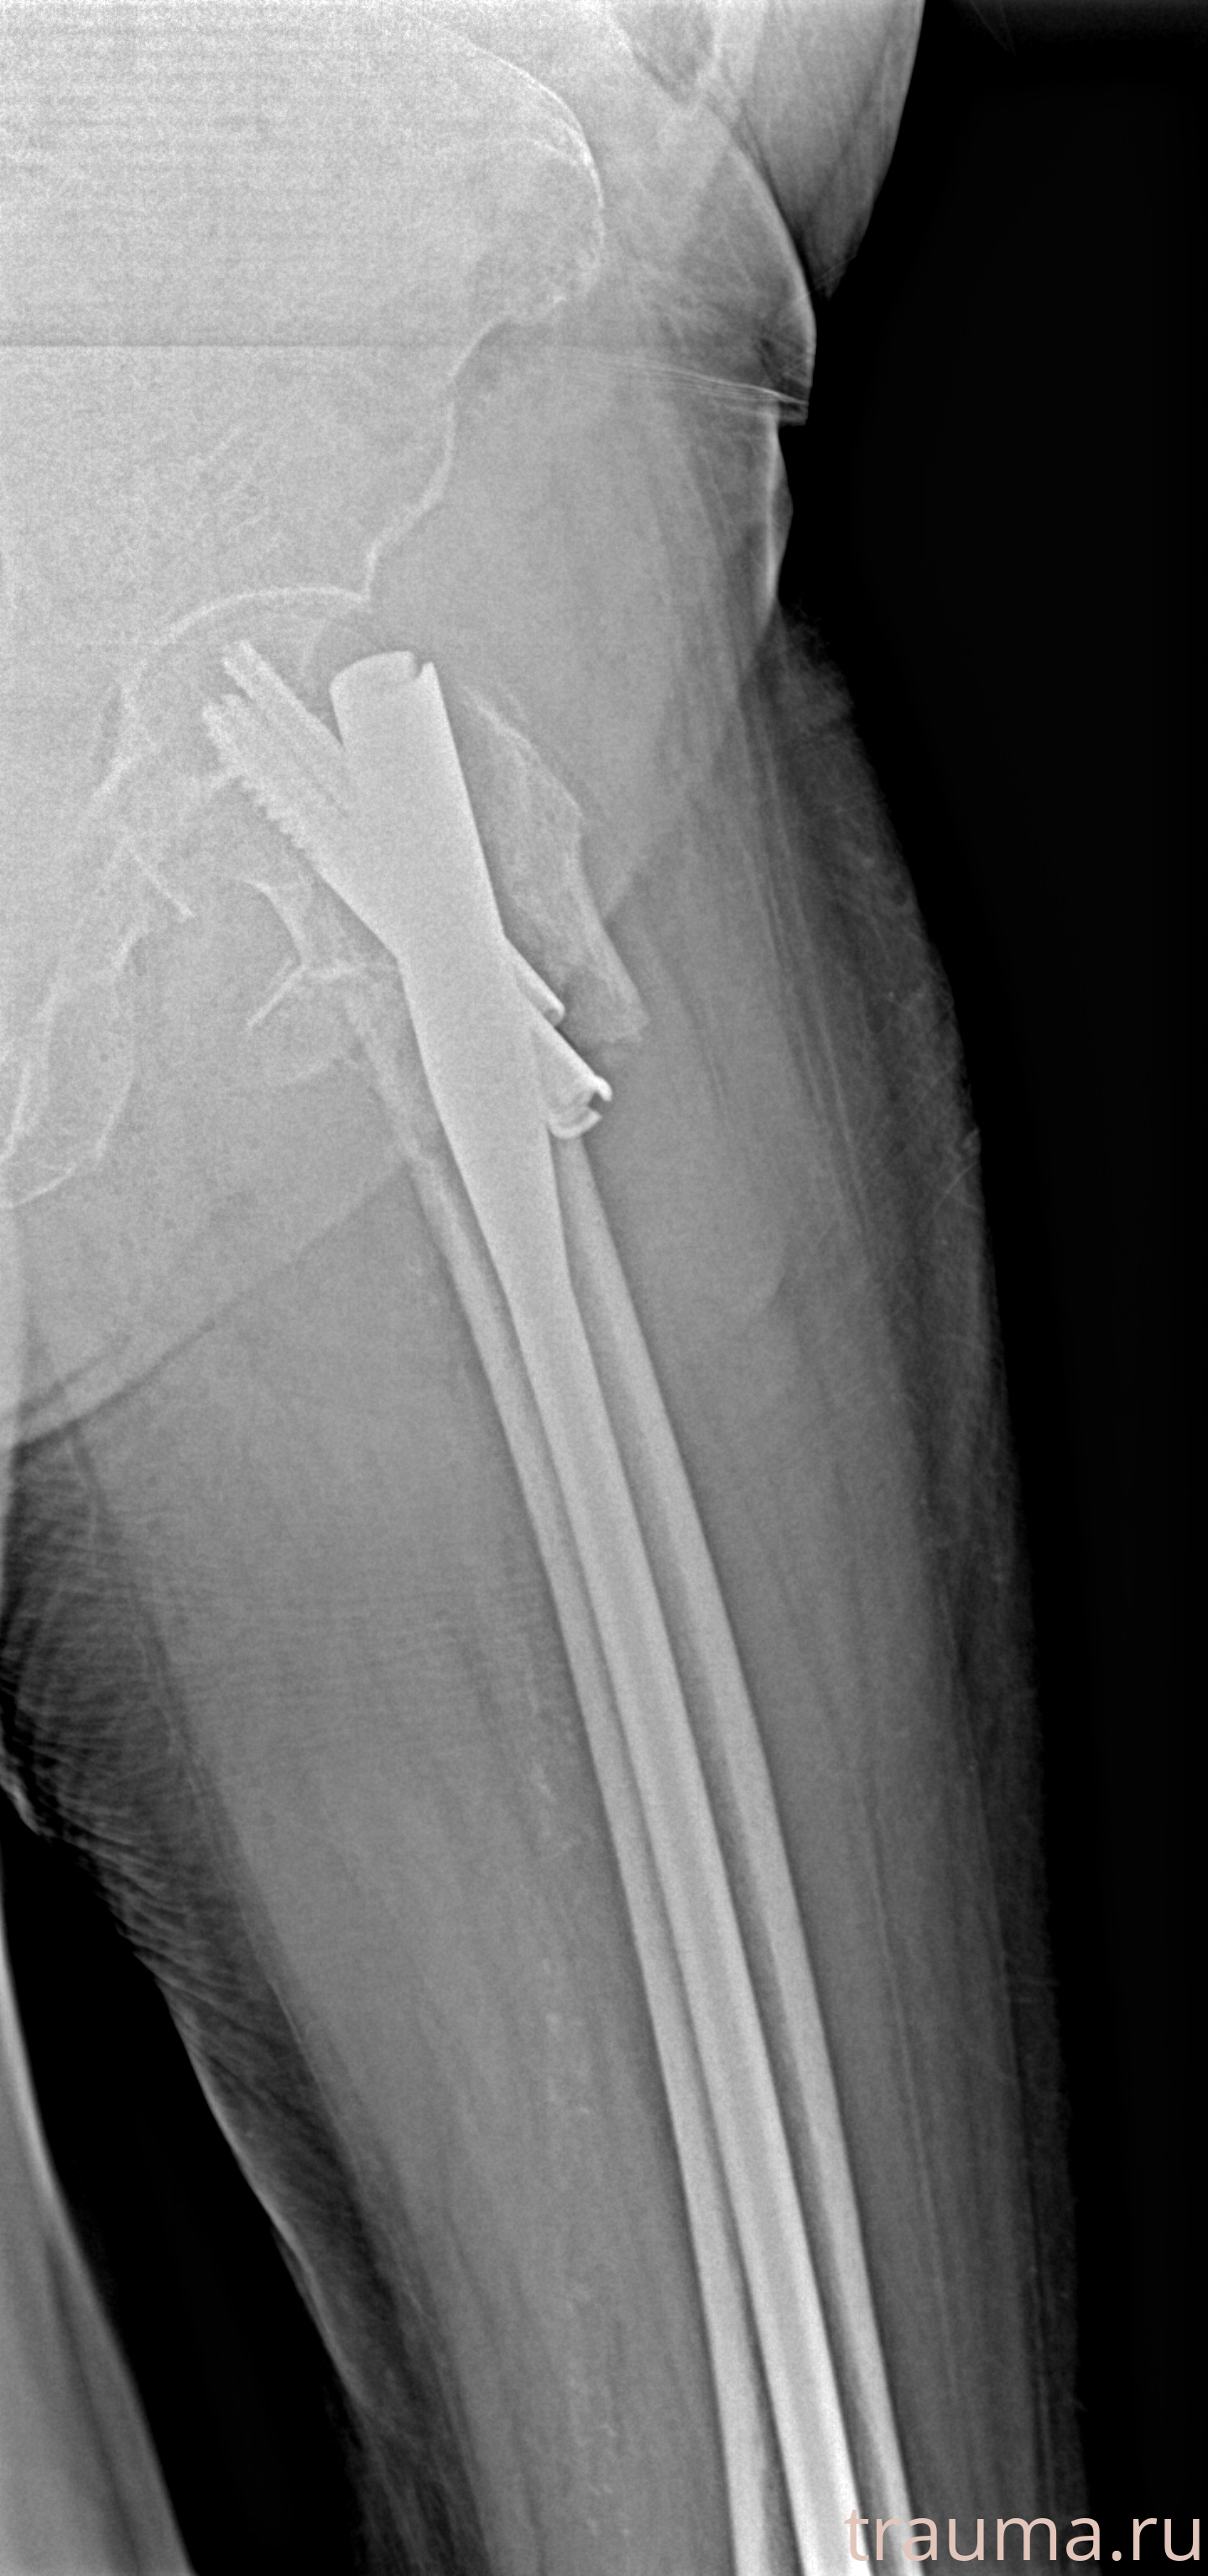

Рентгенограммы

Рентген на дому: по вашему адресу приезжает врач-рентгенолог, травматолог-ортопед с мобильным рентгеновским аппаратом, проводит диагностику травмы или заболевания, делает необходимые рентгенограммы, дает рекомендации по дальнейшему лечению. Получить качественные снимки в домашних условиях возможно благодаря уникальной методике, разработанной МосРентген Центром для института  Склифосовского